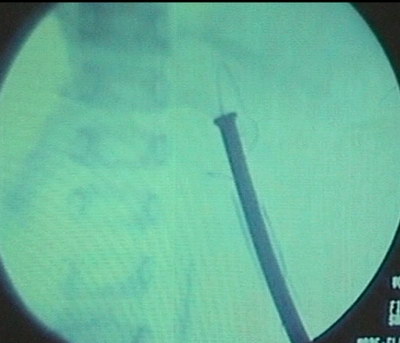

Цистоскоп свободно проведен в мочевой пузырь, катетеризация

мочеточника катетером № 4 F. Типичный доступ в Х межреберье.

Доступ бужирован до 30 F. Нефропиелоскопия по кожуху № 28

F.